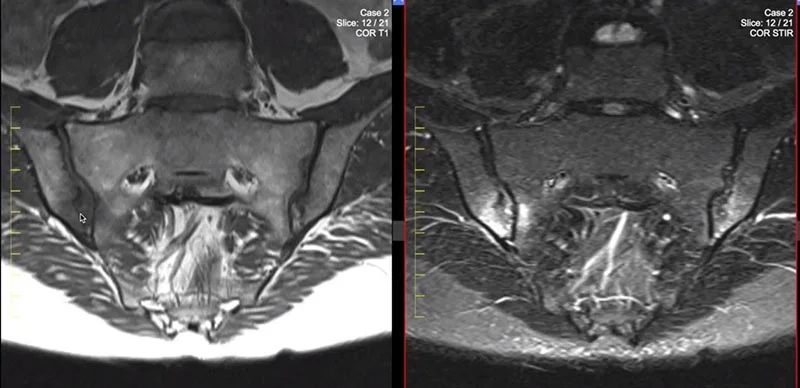

Це МРТ дослідження показує крижово-клубові суглоби, які з’єднують центральну крижову кістку з клубовими кістками таза з кожного боку. МРТ крижово-клубового суглоба – неінвазивна процедура, яка допомагає діагностувати захворювання, пов’язані з основою хребта.

МРТ крижово-клубових суглобів є незамінним методом обстеження для виявлення запальних змін крижово-клубового зчленування. Завдяки використанню спеціальних послідовностей з придушенням сигналу від жирової тканини (STIR), значно зростає чутливість методу до виявлення збільшення вмісту рідини в тканинах (набряку і запалення). Що дозволяє діагностувати сакроілеіт на дорентгенологіческіх стадіях.